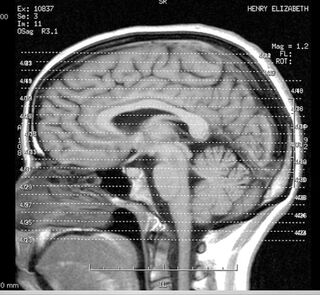

Remember when the only downside to excessive typing was carpal tunnel? Now, experts predict fundamental changes to how we read, think, and learn, all thanks to our technological obsessions. To better understand your changing brain, head to Wilson Sonsini for "iBrain: Surviving the Technological Alteration of the Modern Mind" tonight at 7 p.m. If you want more than a superficial understanding of touch screens, IxDa-SF will be at Particle looking at "Multi-Everything: Multi-touch and the NUI Paradigm" starting at 6:30 p.m. And if a one night isn't enough for you, get your fill of fully immersive environments at the Artificial Intelligence and Interactive Digital Entertainment Conference at Stanford. Game Developers and academics are getting together through Friday to discuss everything from realistic human characters, social intelligence, and Spore! (Photo by Liz Henry)